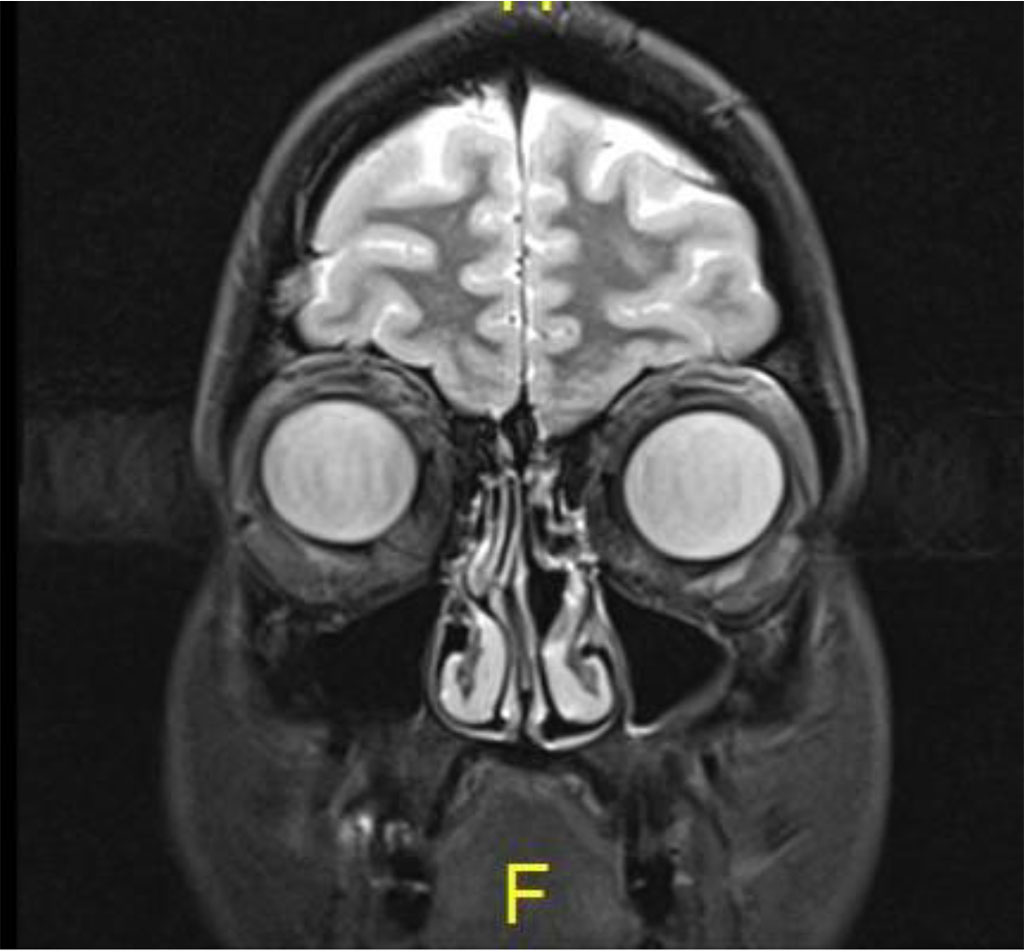

Following the procedure, the patient complained of diplopia in primary position with restriction of upgaze. The patient was treated with oral steroids with no improvement. MRI was 2 months post procedure, there was excellent anatomical improvement, with significant decrease of the lesion but with enlargement of the inferior rectus (Figures 4 a,b,c).

Figure 4c: Coronal MR T2: Complete resolution of lesion